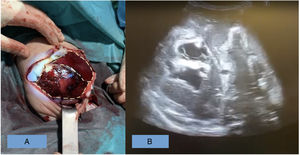

Caso 2. Mujer prematura de 31+4 semanas ingresada en la UCI neonatal por prematuridad y distrés respiratorio con evolución favorable. El noveno día de vida presenta hipotensión, anemia y distensión abdominal rápidamente progresiva. Se decide laparotomía urgente tras el fracaso de las medidas médicas de reanimación. Se evidencia un hemoperitoneo masivo, con restos de nutrición parenteral, secundario a un estallido hepático derecho. Se observa laceración hepática de 8cm en los lóbulos vii-viii, con otra mínima laceración a nivel lateral del segmento vi, ambas con sangrado activo. El eje vascular portal estaba íntegro y la hipoperfusión intestinal era generalizada. Se establece como causa del estallido hepático la extravasación intraparenquimatosa de la nutrición parenteral administrada por vía umbilical. Se llevan a cabo distintas técnicas hemostáticas sin éxito, finalizando la intervención con un packing abdominal para revisión posterior. En las horas siguientes la paciente presenta empeoramiento clínico, fracaso multiorgánico y finalmente exitus (figs. 1 y 2).

Correlación clínico-radiológica. En la figura 2A se observa la diferencia entre hígado derecho (presencia de quiste de nutrición parenteral y estallido hepático superficial con zonas hipoperfundidas) e hígado izquierdo (sin hallazgos). En la figura 2B se observan los quistes intraparenquimatosos y líquido libre.